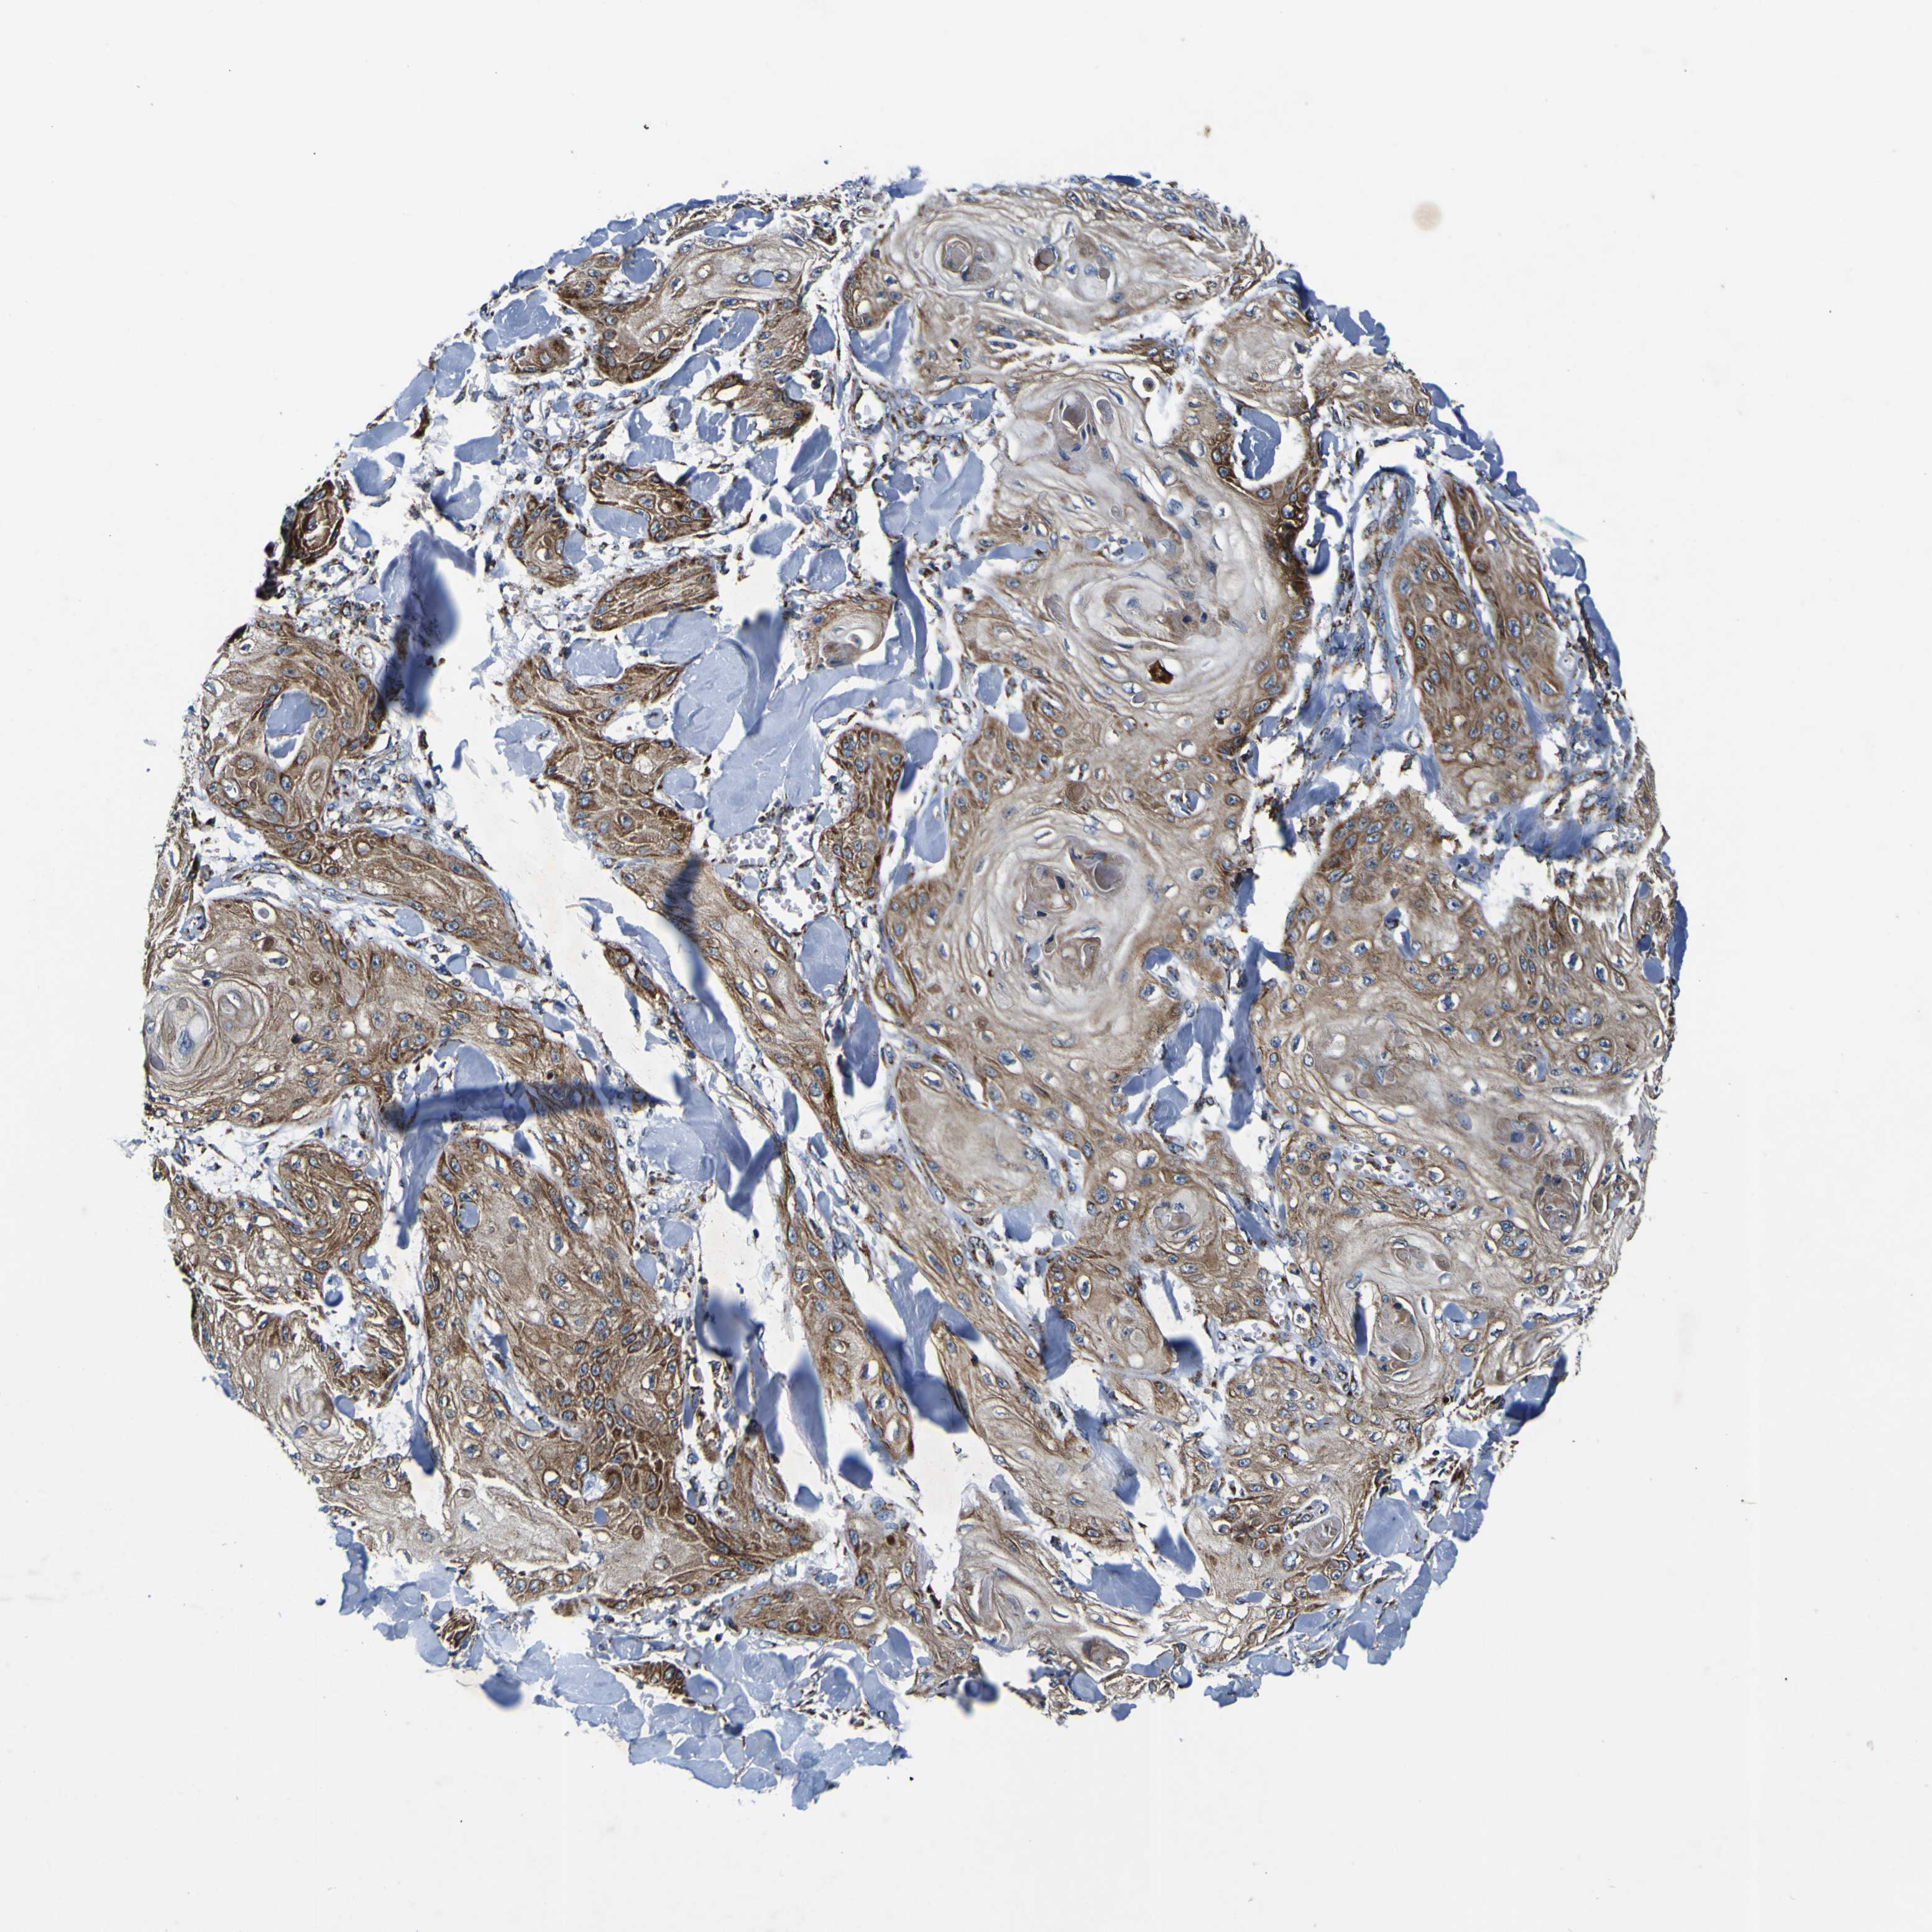

SKIN CANCER - Protein expressioni

A mouse-over function shows sample information and annotation data. Click on an image to view it in a full screen mode. Samples can be filtered based on level of antibody staining by selecting one or several of the following categories: high, medium, low and not detected. The assay and annotation is described here.

Each image is clickable and will lead to virtual microscopy that enables deeper exploration of all samples and also displays staining intensity scores, fraction scores and subcellular localization as well as patient and tissue information for each sample.

Antibody HPA012897

Staining

High

Medium

Low

Not detected

Intensity

Strong

Moderate

Weak

Negative

Quantity

>75%

75%-25%

<25%

None

Location

Nuclear

Cytoplasmic/membranous

Cytoplasmic/membranous,nuclear

Squamous cell carcinoma, NOS